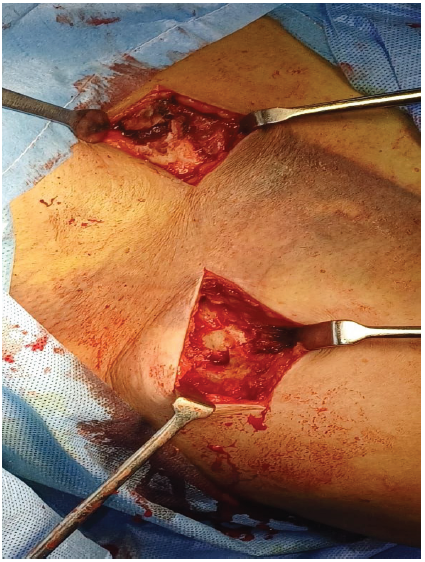

The patient underwent open reduction and internal fixation under general anesthesia. The patient was placed in a modified beach chair position during the procedure. No single clavicular plate was available that could fix the bipolar clavicle fracture, so planned fixation with two separate plates. A 5 cm incision was made over the medial third of the clavicle [Fig. 4], the fracture was reduced, and it was fixed with a 3-hole opposite side lateral clavicular locking compression plate (LCP) (3.5 mm–2.7 mm system).

Figure 4: Exposure of fracture site, lateral and medial incision over fracture site.

Subsequently, a 7 cm lateral clavicular incision was made, and the fracture was reduced and fixed with a 4-hole right lateral clavicular LCP [Fig. 5].